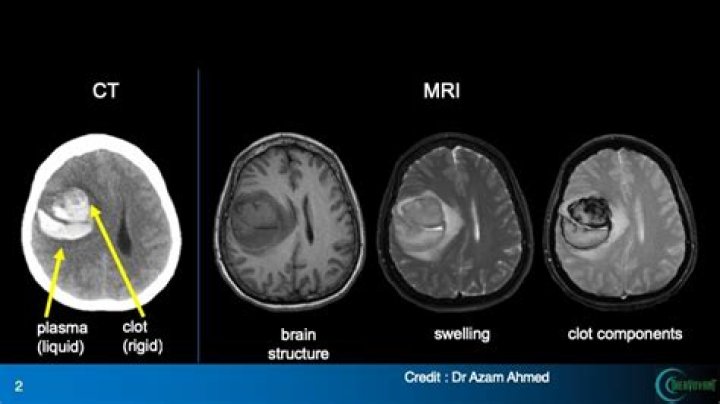

A ministroke doesn't typically lead to permanent brain damage, but you still need an urgent medical examination if you have symptoms of a ministroke. The only way to tell the difference between a ministroke and a stroke is by having a doctor look at an image of your brain with either a CT scan or an MRI scan.